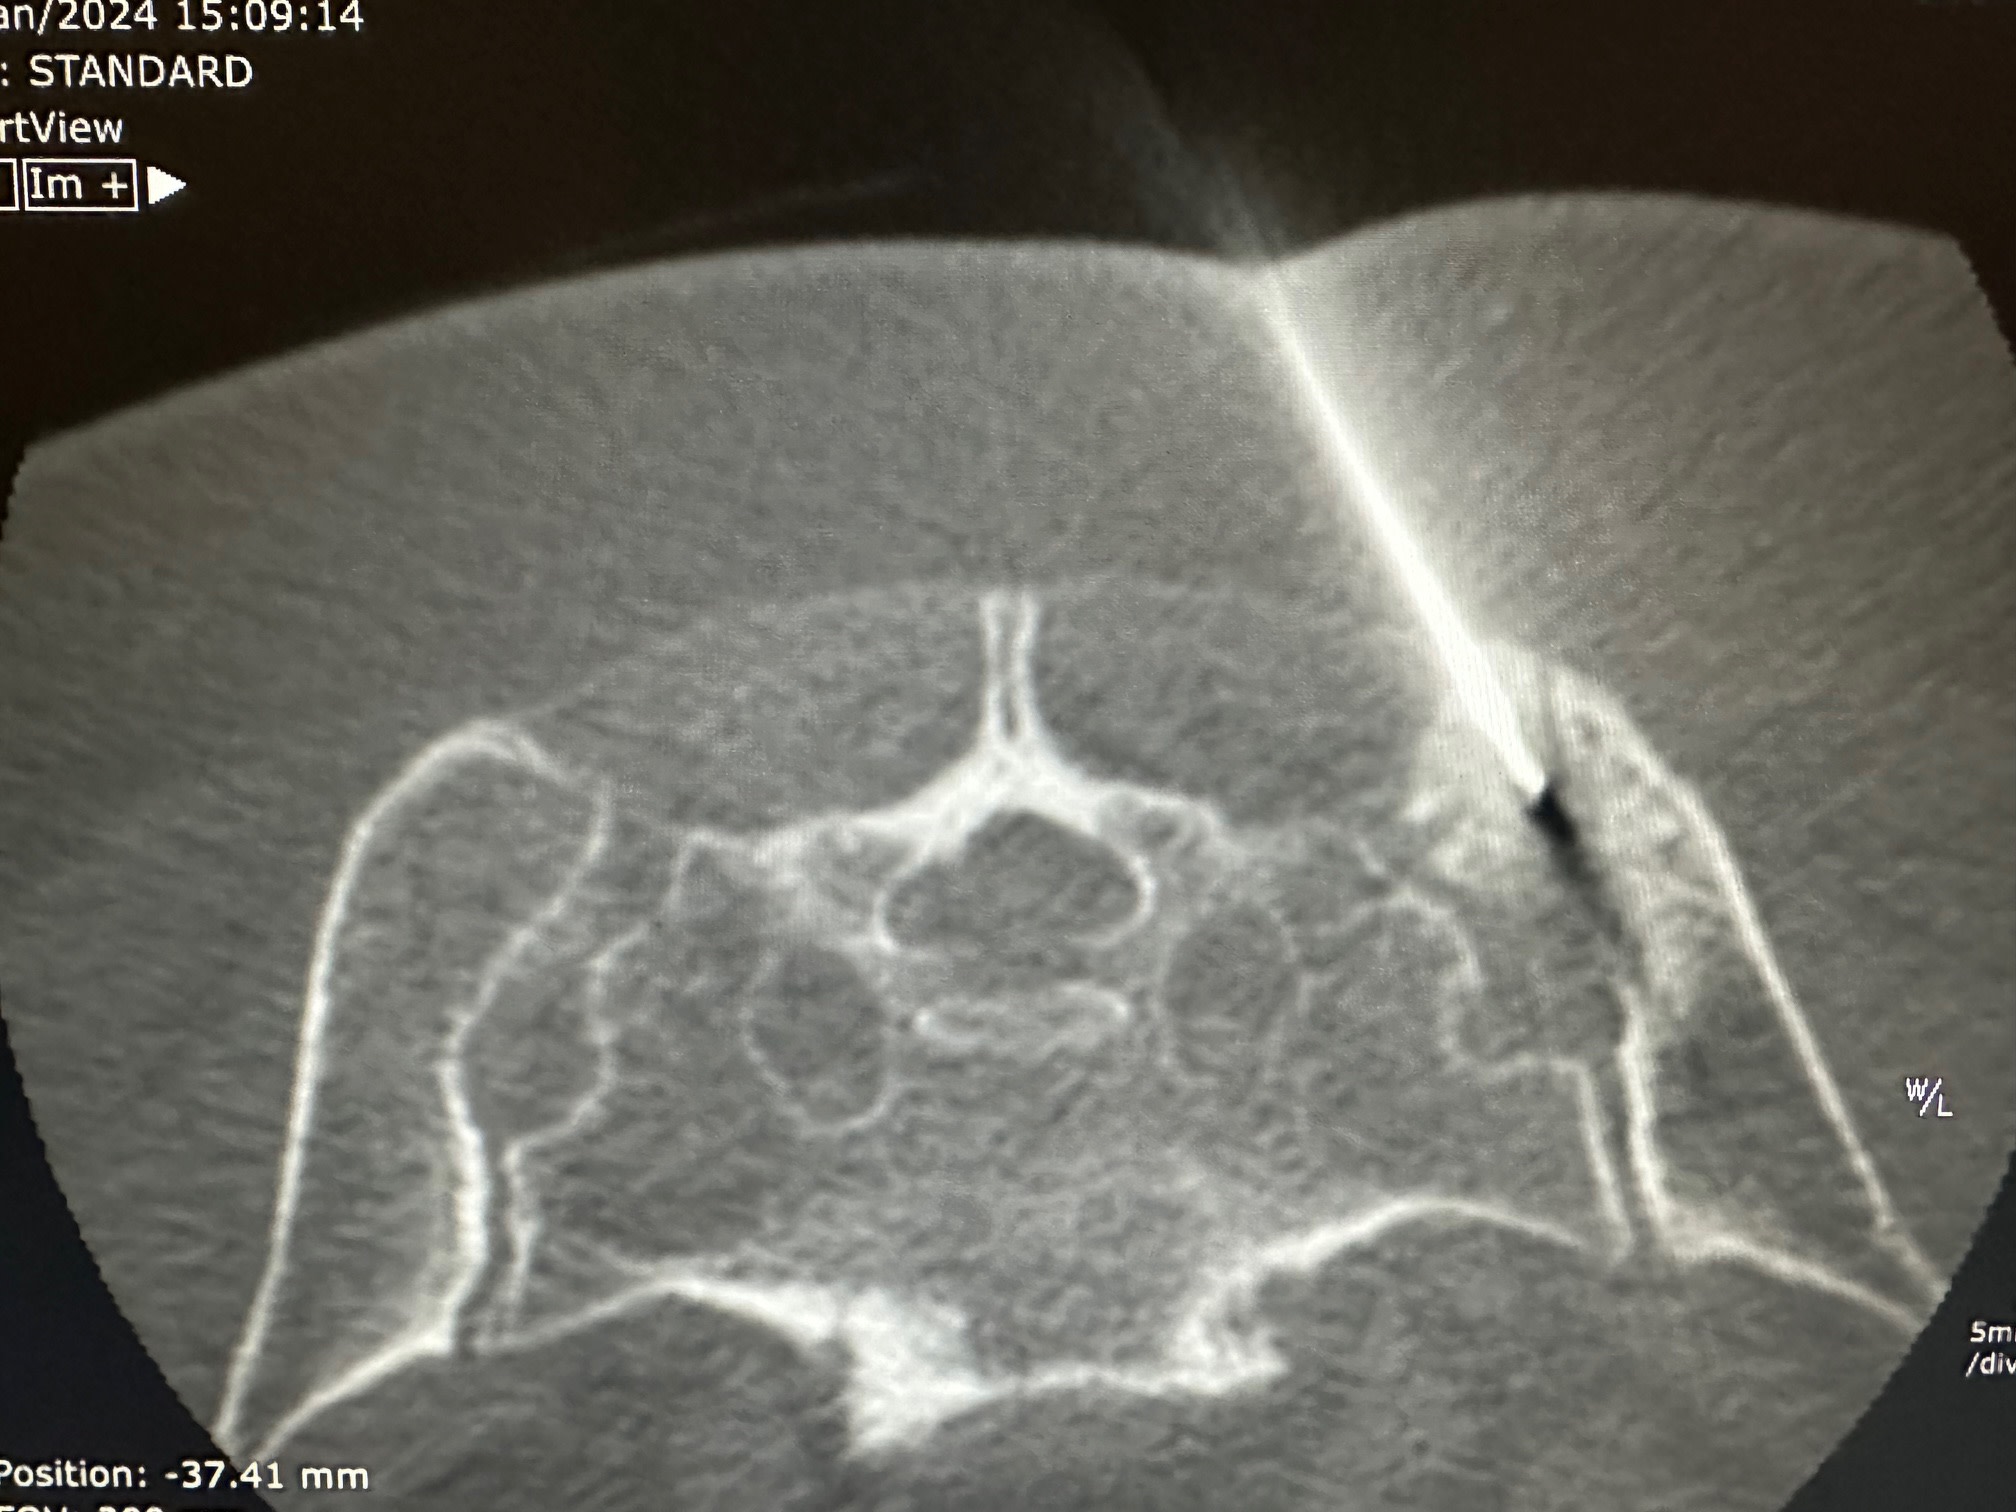

Les interventions, effectuées sous sédation, anesthésie locale ou, plus rarement, anesthésie générale, consistent à insérer des aiguilles dans la tumeur, sans nécessiter d'incision chirurgicale, sous contrôle et guidage précis par scanner dans notre salle dédiée.

À l'extrémité de ces aiguilles, un glaçon se forme, atteignant une température comprise entre -20 et -40°C, entraînant la mort des cellules tumorales.

L'un des principaux avantages de cette technique réside dans sa précision, permettant aux radiologues interventionnels de visualiser en temps réel la formation du glaçon de cryothérapie au sein de la tumeur, assurant ainsi une efficacité optimale de la destruction tout en préservant au maximum les tissus sains environnants.